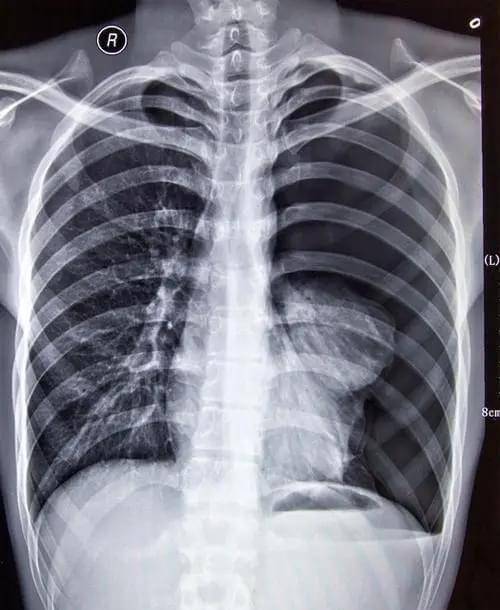

胸片:肺气肿.